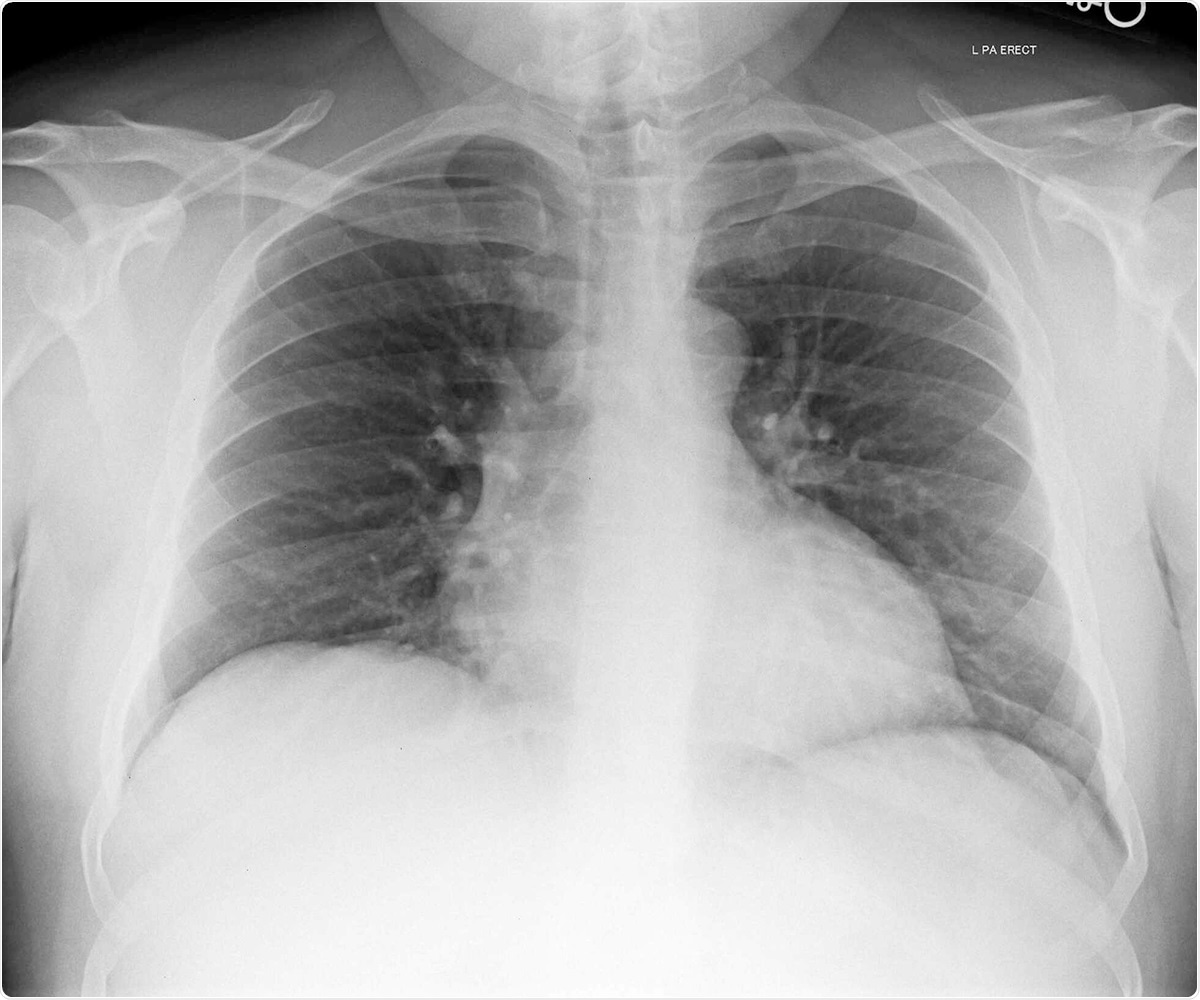

• Chest X-ray showed reduced lung volumes

Chest X-ray image of patient 3. Image Credit / Original Article.